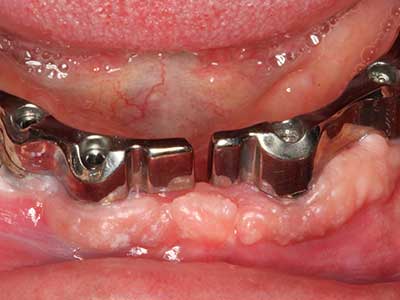

Indication: Periodontal therapy

Marginal periodontal diseases are the main reason for extractions in advanced age. These diseases are primarily caused by bacterial colonization of the gingival pocket, which causes inflammation followed by loss of the periodontium. The formation of subgingival biofilms and concrements is a significant aetiological factor for marginal bone atrophy, so their removal is an important part of the treatment (Drisko 2014, Plessas 2014).

Initial and surgical treatment phases are differentiated in the treatment of marginal periodontitis. In addition to instruction in oral hygiene and motivating patients, both phases should include adequate cleaning of the root surface. In the regenerative setting an open access is generally preferred. The root surface can be cleaned by piezo surgery using special attachments, where instruments with different curvatures are used to reach areas that are difficult to access, such as furcations. The integrated irrigation in the system flushes the detached concrements and bacteria out of the pocket. Specialized systems such as the Piezomed also include application feedback to minimize the ablation of hard dental substance. The greater the pressure on the periodontal attachment the greater the reduction in the amount of ablation.